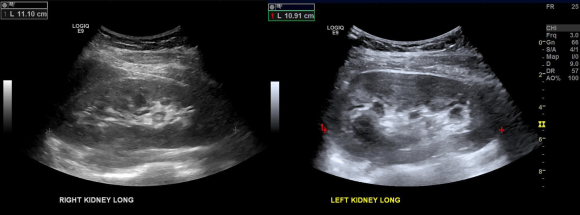

I ordered a renal duplex and a CT venogram for procedural planning.

On the duplex, the proximal left renal vein (LRV) was not visualized. The right kidney had normal parenchymal appearance and blood flows, while the left, the kidney appeared distended and had flows consistent with outflow obstruction.